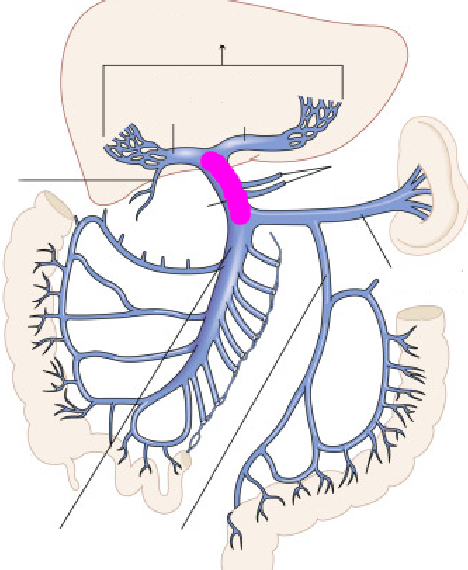

Inferior vena cava

Hepatic artery

Hepatic portal vein